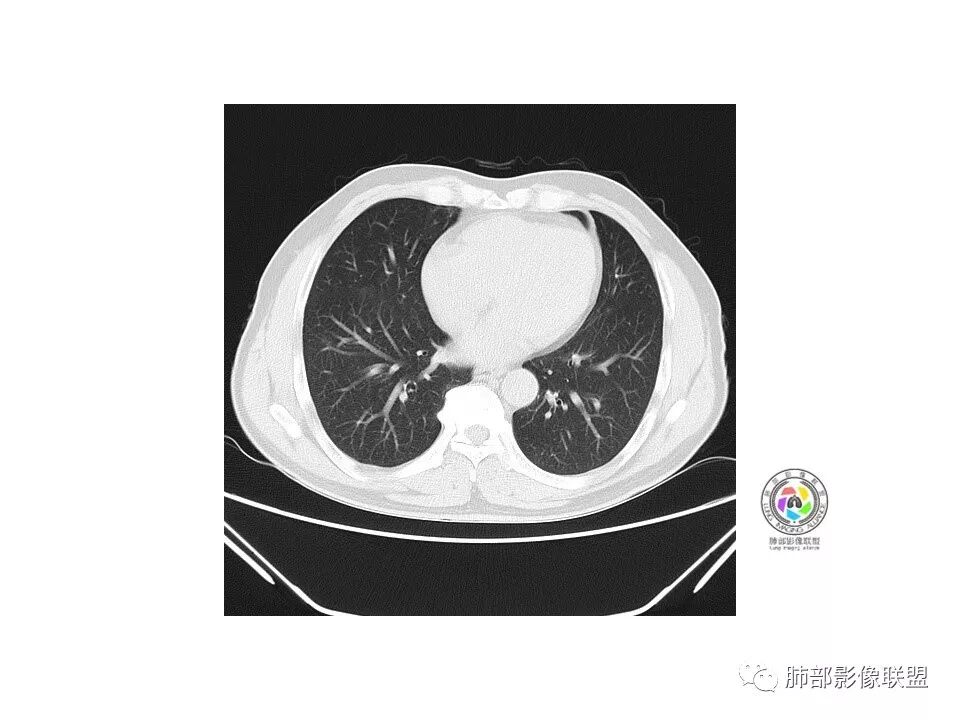

张立:

右肺下叶混合磨玻璃密度结节,有月牙铲,内可见血管,血管移动联通,常规消炎复查,还存在考虑AIS-MIA

go and see:

患者老年男性,右下肺前基底段靠近胸膜侧可见一个mGGO结节,边缘清淅,可见分叶征及月牙铲,小结节病灶胸膜牵拉明显,首先考虑MIA可能性大。

弹指之间:

右肺下叶mGGO,边缘清晰,浅分叶,内血管影增粗,见点状实性成分,小支气管牵拉扩张,考虑MIA,建议抗炎后复查。

张小兵:

右肺下叶前基底段mGGN,边界清晰,内部结构杂乱,见网格空泡感,月牙铲,浅分叶及胸膜牵拉,倾向MIA。

Shelia??:

右肺下叶GGO,边缘清晰,有月牙铲,有血管进入,内部结构紊乱,胸膜牵拉,考虑MIA,常规建议抗炎治疗后复查。

崇军:

右肺下叶磨玻璃结节,边界清晰,边缘有分叶及月牙铲,并可见轻度胸膜牵拉,收缩力弱,有血管移动联通征,而且病灶内血管影轻度增粗,实性成分很少,考虑AIS,可以让子弹再飞一会,或常规抗炎治疗后复查。

欣:

界清ggo,月牙铲,考虑腺癌

欧阳英:

右肺下叶前基底段磨玻璃小结节,其内血管稍增粗,边缘见分叶、月牙铲,考虑ais,炎性结节不排

有增粗,联通、移动,高度怀疑Ca,常规抗炎后复查

病理结果

腺癌